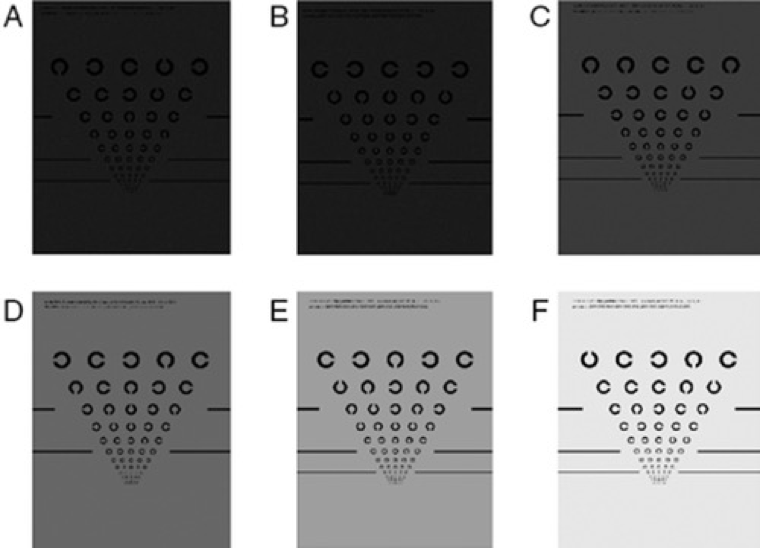

Sehschärfe unter geringer Leuchtdichte (LLVA)

Die Sehschärfe von Menschen mit AMD ist bei schlechten Lichtverhältnissen in der Regel eingeschränkt.8 Bei einem Sehschärfentest unter geringer Leuchtdichte wird das Sehvermögen bei schwacher Beleuchtung geprüft. Ähnlich wie bei der Überprüfung der Bestkorrigierten Sehschärfe (BCVA) sehen sich die Patienten eine Sehtest-Tafel an. Bei der LLVA-Untersuchung werden jedoch Filter verwendet, die die Lichtverhältnisse anpassen.16 Der gemessene Unterschied zwischen der Bestkorrigierten Sehschärfe (BCVA) und der Sehschärfe unter geringer Leuchtdichte (LLVA) wird berechnet und als sog. „low luminescence deficit (LLD)“, dem Defizit unter geringer Leuchtdichte, angegeben.17 Der LLD-Wert eines Patienten kann mit AMD-Läsionen korrelieren.17 Patienten mit einer AMD im frühen Stadium schneiden bei einer LLVA-Untersuchung meist schlechter ab als bei der BCVA-Untersuchung.17